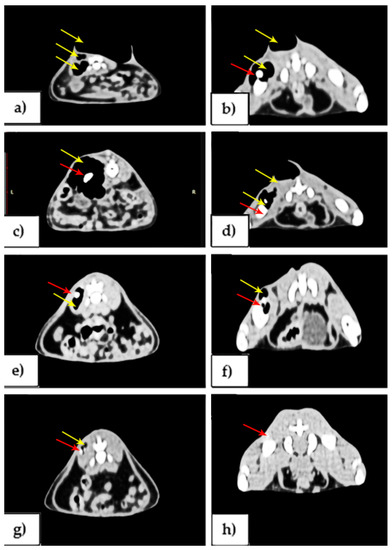

3.2. Imagistic Results